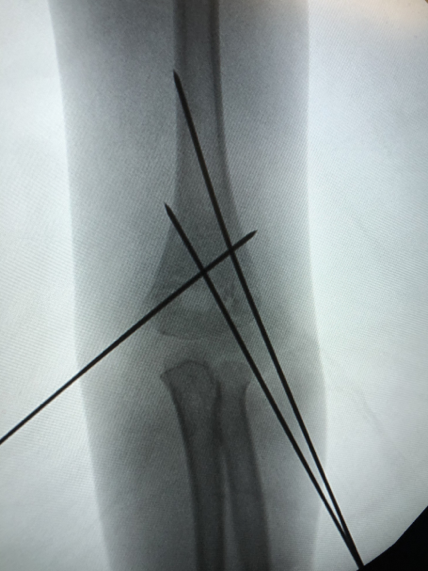

小儿骨科康映泉副主任医师接诊后确诊是“肱骨髁上骨折”,骨折完全移位,所幸没有血管神经损伤,但仍需要手术治疗。康映泉副主任医师应用最新治疗手段,即超声引导骨折复位技术,大大降低术中辐射暴露,成功为小晨施行骨折闭合复位内固定术,术中没有伤口,针尾留置皮肤外面,待1个月后骨折愈合即可门诊拔除,无需住院或麻醉,看着无大碍的孩子,小晨爸爸悬着的心终于放下。

▲超声引导下骨折闭合复位钢针内固定及术后外观照

康映泉副主任医师介绍,自去年开始,我院小儿骨科已成功开展数十例超声引导下儿童四肢骨折微创复位、内固定,包括肱骨髁上骨折、肱骨外髁骨折、尺桡骨骨折、胫腓骨骨折等,应用超声引导技术,极大降低术中辐射暴露,特别是对于儿童患者,低辐射手术对其生长发育具有至关重要的作用。

▲超声引导下骨折闭合复位钢针内固定术